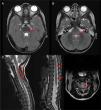

Neurologic disease associated with enterovirus D68Neurologic disease associated to infection by EV-D68 is different and less frequent (5 confirmed cases since late 2015 in Spain). However, it has been widely covered by the media due to its severity, comparable to that of poliomyelitis. Its manifestations often complicate lower respiratory tract infections. The clinical presentation consists of acute flaccid paralysis and arreflexia. Neuroimaging (Fig. 1) reveals longitudinally extensive myelitis with predominant involvement of the anterior horn. Features of rhombencephalon involvement are indistinguishable from those caused by EV-71. Electromyography can confirm motor neuron damage at one week from onset and signs of denervation at three to four weeks. The prognosis is very poor, with a high mortality and variable degrees of flaccid tetraparesis and involvement of respiratory muscles.

Rhombencephalitis caused by EV-D68: T2-weighted brain and spinal cord MRI scans obtained during the acute phase of disease. The arrows point at dorsal involvement at the level of the pontine (A) and bulbar tegmentum (B) as well as the entire medulla oblongata (C) with grey matter predominance (D) (Courtesy of Ignacio Delgado, Radiology Dept.).